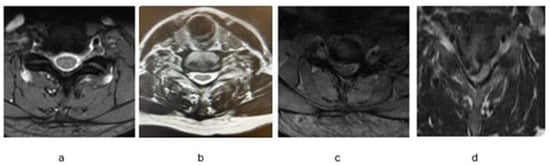

2.4. MRI Evaluation